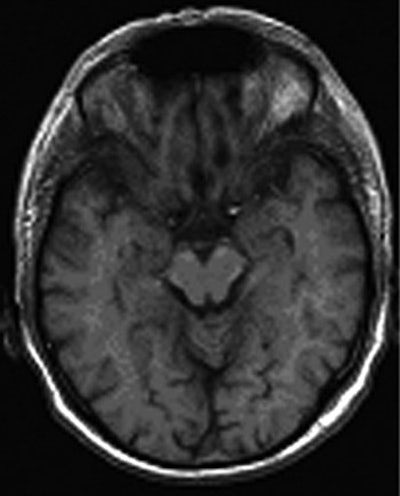

![]() |

| Fifty-one-year-old male smoker with hyperlipidemia. T1-weighted FLASH image of brain parenchyma shows normal findings (AJR 2005; 184:598-611). |

Cerebral MRI

The cerebrum was assessed by T1- and T2-weighted fast spin-echo, FLAIR, and diffusion-weighted imaging. The intracerebral arterial system was directly visualized by axial 3D time-of-flight MR angiography.

Screening for cerebral tumours was done using a contrast-enhanced cerebral sequence. Repeat administration of contrast was avoided by performing the scan after the cardiac exam, so the contrast administered for MR angiography was also used for the cerebral sequence.